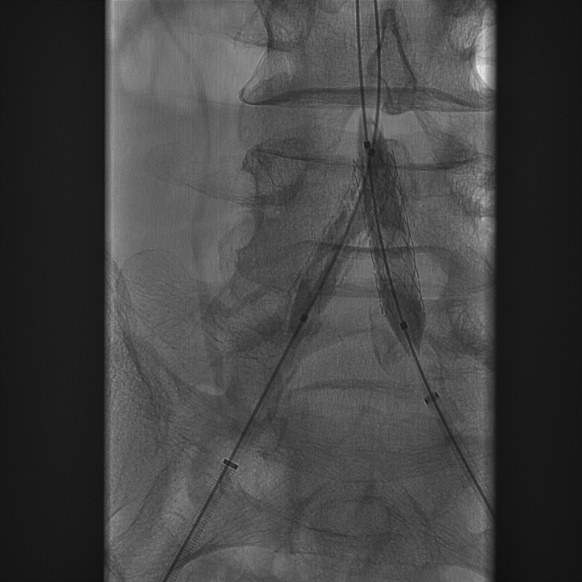

(3)建立右侧股总动脉逆行入路后,泥鳅导丝配合VER导管通过髂总动脉病变后,双侧入路交换为260cm加硬泥鳅导丝,随即透视监视下导入 8F*45cm长鞘至双侧髂外动脉近端;延右侧导丝进入INVETEC 5*40mm球囊行右侧髂总动脉狭窄病变预扩张。

导丝怎么扩【问术ASK】佟铸教授:双侧髂总动脉“对吻”球扩覆膜支架植入术_https://www.jmylbn.com_新闻资讯_第5张